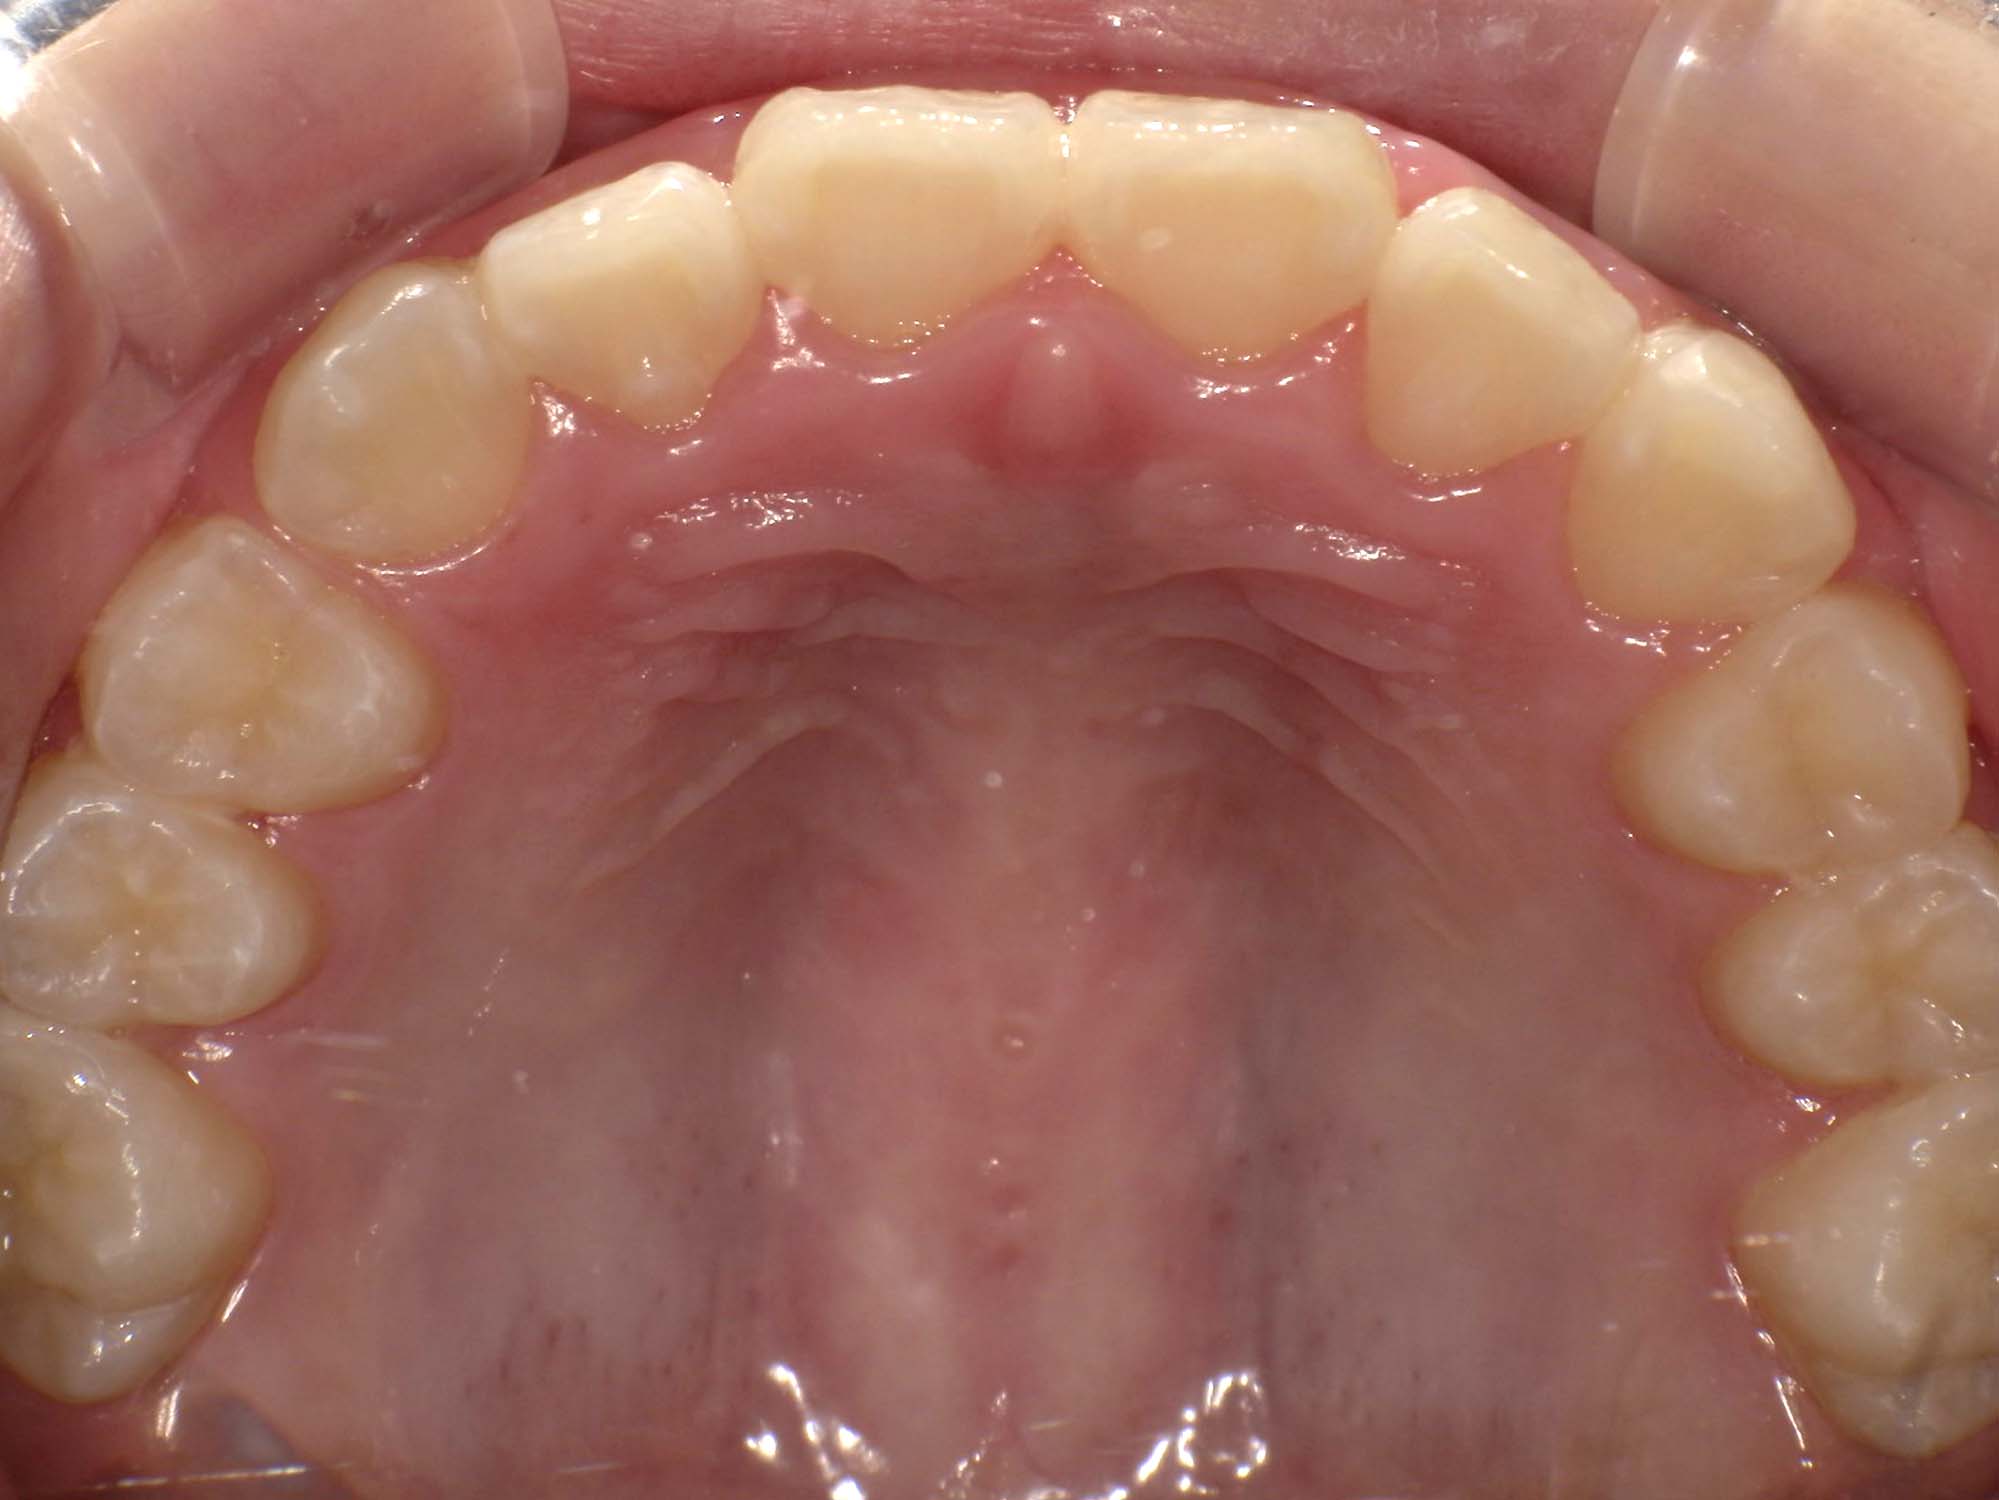

| 年齢・性別 | 8歳9ヶ月の女児 |

|---|---|

| 主訴 | 歯並びの乱れを気にされて来院された患者様です。将来的なスペース不足と歯のねじれ(翼状捻転)が懸念されました。 |

| 治療期間・回数 | 2年10ヶ月・19回 |

| 費用 | 430,000円(税別) |